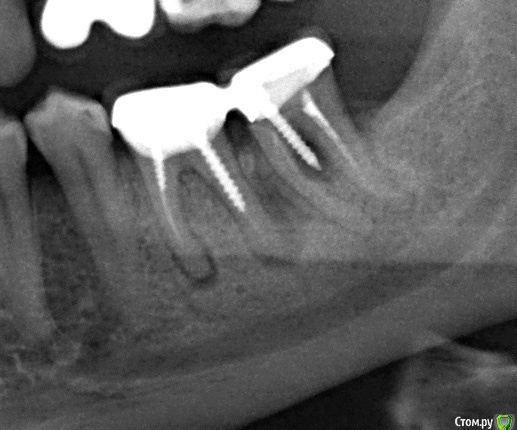

Nighten Опубликовано 6 сентября, 2017 Поделиться Опубликовано 6 сентября, 2017 День добрый! Итак, гранулёма. Да, знаю, что штифт тоже сделан криво. Но, по гранулёме: неужели современная медицина не может предложить ничего, кроме удаления??? Ссылка на комментарий

DmitrySH Опубликовано 7 сентября, 2017 Поделиться Опубликовано 7 сентября, 2017 День добрый! Итак, гранулёма. Да, знаю, что штифт тоже сделан криво. Но, по гранулёме: неужели современная медицина не может предложить ничего, кроме удаления???Сложность не в гранулеме, а в ненадежности самих зубов после лечения. Ссылка на комментарий

dok1 Опубликовано 7 сентября, 2017 Поделиться Опубликовано 7 сентября, 2017 В вашем случае - в зубе, где "штифт криво" ничего нельзя сделать кроме удаления. 4 Ссылка на комментарий